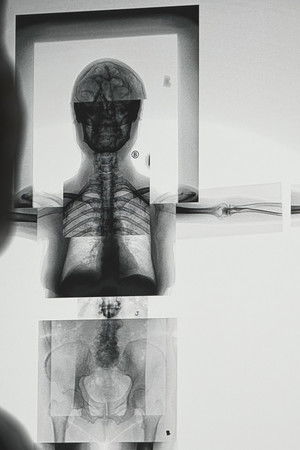

A documentary about an exhibition and the people behind it.